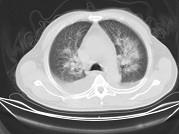

男,32岁,CT图像如图,最可能的诊断为 ( )A.肺水肿并双侧胸腔积液B.周围型肺癌C.肺动静脉瘘D.肺错构瘤E.炎性假瘤

问题 男,32岁,CT图像如图,最可能的诊断为 ( )

选项 A.肺水肿并双侧胸腔积液 B.周围型肺癌 C.肺动静脉瘘 D.肺错构瘤 E.炎性假瘤

答案 A